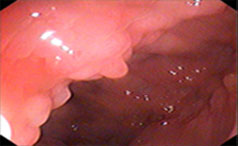

一般来说胃息肉的患者没有太多典型的症状表现,但是随着疾病的逐步发展或严重,胃息肉的患者可能会出现食欲减退、消化不良、胃部疼痛、恶心呕吐、腹胀......【详情】

常见症状:上腹隐痛、腹胀、不适

无痛性便血、脱垂

胃肠息肉的危害有哪些?

胃息肉可以引起上腹部的不适、消化不良、消瘦等,严重的可能引起癌变...【详情】